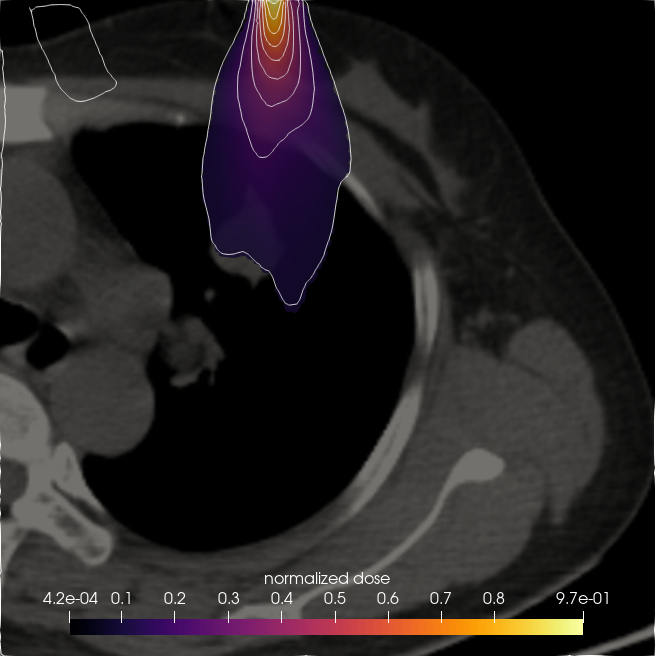

7.3. Beam in 2D patient CT

Having validated the CSD solvers against StarMAP and a Monte Carlo framework in section 7.1, we now examine a realistic 2D CT scan of a lung patient as a proof of concept for the application of our framework to radiation therapy computations. The patient data was retrieved from an open source data set (Li et al., 2020) in The Cancer Imaging Archive (TCIA) (Clark et al., 2013). The patient is irradiated with an electron beam of MeV. We model this beam as the initial condition

where is the beam position within the domain and is the beam direction. The remaining parameters are chosen as . To determine a tissue density for given gray-scale values of the CT image, we set the maximum density, represented by white pixels, to the density of bone . The remaining tissue is scaled such that the minimum pixel value of zero corresponds to a minimal density of . This corresponds approximately to the lower bound of observed lung densities (Kohda and Shigematsu, 1989).

Figure 14 compares the normalized dose for a CSD , and solver. While all methods show similar behaviour and are able to capture the effects of heterogeneities in the patient density, some differences e.g. in the maximum depth of the solution compared to and or the shape of the lowest two isolines can be observed. The cross sections in figure 15 further show that the dose has a lower maximum and higher minimum value than the and to a lesser extent also solutions.